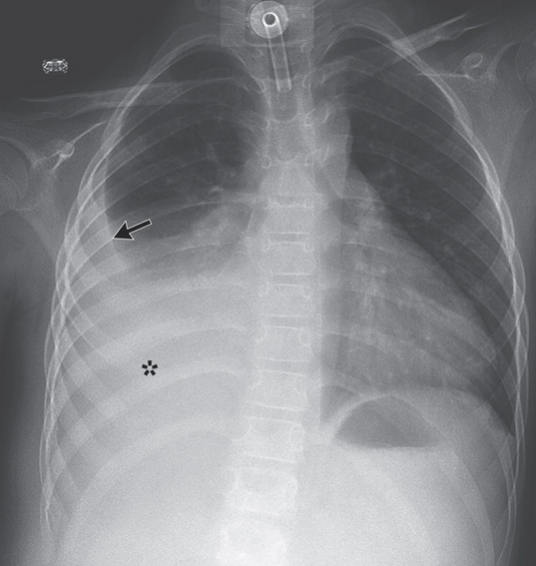

胸壁肿瘤是指胸廓深部软组织、肌、骨骼的肿瘤。可分为原发性和转移性两类,原发性胸壁肿瘤又分为良性及恶性两种。原发于骨组织者,多发生于肋骨。发生于前胸壁及侧胸壁者多于后胸壁。转移性肿瘤系从他处恶性肿瘤转移而来,以转移至肋骨多见。